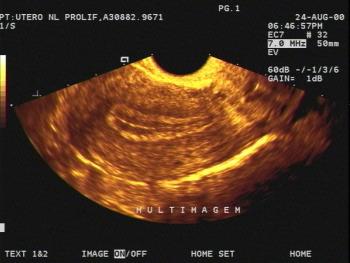

Gynecology Images: Normal Abnormal Obstetric Images: 1st Trimester: Normal Abnormal 2nd Trimester: Normal Abnormal 3rd Trimester: Normal Abnormal Medical Professionals: Upload Your Here Obstetric Images: 3rd Trimester: Normal Normal Thymus - Albana Cerekja Fetal urethra at 31 weeks: just before micturition - Albana Cerekja Normal Female: 4D still image - Effendi Mansoor Monolateral double renal artery,: Normal variant kidney artery supply - Albana Cerekja TRV Fetal Head: BPD and HC Measurements - SIEMENS Velamentosa insertion: 3rd trimester - Effendi Mansoor Umbilical Cord (3D Surface Rendering): Normal Cord - MEDISON SAG Fetal Face, Profile: Fetal Breathing on Color Doppler - SIEMENS 3D Surface Reconstruction: Face - Cayrol Guillermo 3D Surface Reconstruction: Extended Breech Presentation - Saied Mohamed Tohamy 3D Surface Reconstruction: Face - Juan Carlos Pons 3D Surface Reconstruction: Face and Foot - Cayrol Guillermo 3D Surface Reconstruction: Face - Juan Carlos Pons 3D Surface Reconstruction: Face - Juan Carlos Pons